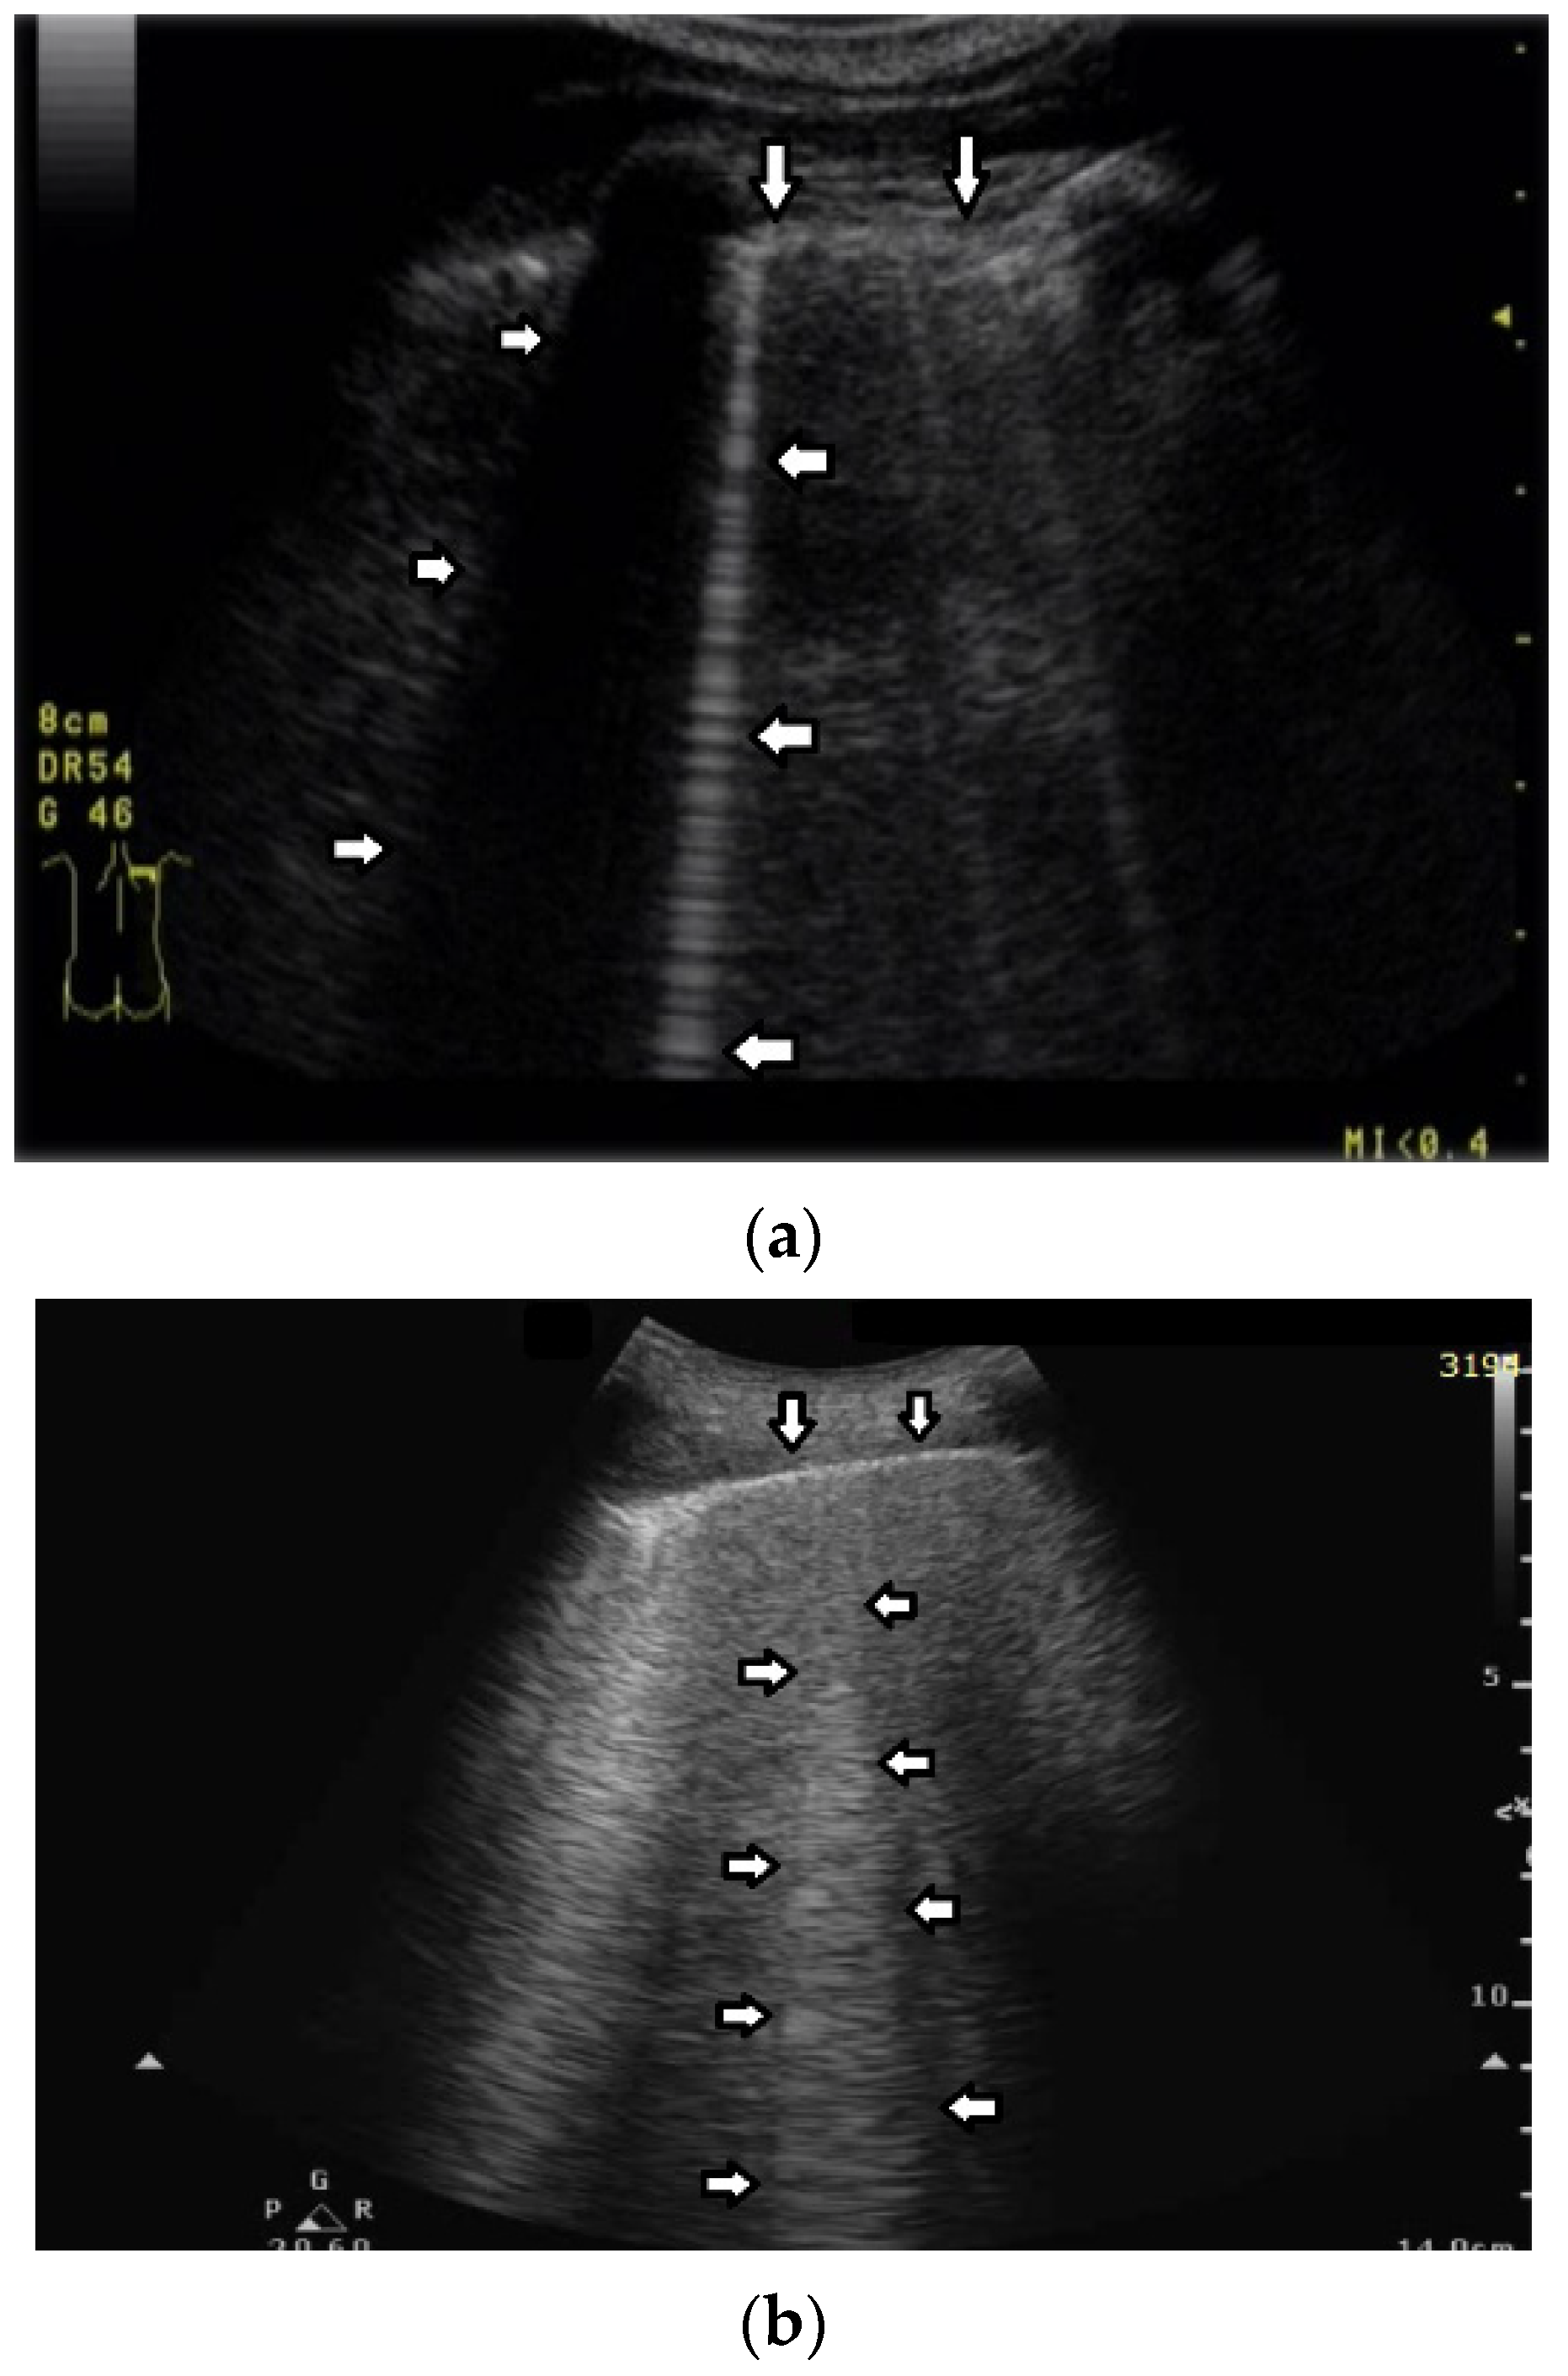

Short vertical artifacts (e.g., the so-called I or Z lines) have never been studied thoroughly. The length of vertical artifacts can vary even in the group of artifacts, which does not reach the bottom of the screen (see Figure 3a,b). One example is the early stage of developing atelectasis (during general anesthesia). What are the most important factors that influence the length of vertical artifacts?

The length of an artifact, as well as its structure and its brightness, depends on so many factors that it is nearly impossible to list them all [18,19]. Generally speaking, the length of a vertical artifact is given by the time an acoustic trap needs to reradiate the pulse energy, which has been partially trapped therein previously. The length of a vertical artifact not only depends on the geometric characteristic of the acoustic trap but also on the imaging parameters. Therefore, the same acoustic trap may give rise to vertical artifacts with different lengths. The imaging parameters play a fundamental role in the formation of the artifacts and the visibility of a vertical artifact (that is, its brightness, lateral dimension, and length) depends on multiple non-orthogonal factors including the gain, the time gain compensation (TGC), and all the parameters that can be easily set by the operator from the scanner keyboard. Therefore, given the intrinsic variability of the artifacts as a function of multiple nonindependent factors, including the human factor, making an objective diagnosis on the basis of the artifactual information is a difficult task. However, going back to your primary question about the length of the shorter artifacts, I can formulate some hypotheses. First of all, we must answer another question: why are they so short with respect to the artifacts that physicians classify them as “artifacts that extend to the bottom of the screen”? Maybe their linking channel is so small that it allows the transmission of a minimal part of the pulse energy, but in this case, a modulated artifact should appear since this is the peculiarity of a small channel [20]. If a confused artifact is generated, then its minimal length can be related to a wide channel with respect to the core of the trap, which allows a quick release of the trapped energy or a dispersion of the trapped energy through lateral doorways. Attenuation can also theoretically account for a minimal length of the artifact, but in this case, I do not have a valid hypothesis on the nature of the medium.

Figure 3. (a) Vertical artifact (←) originating from the pleural line (↓), smooth in structure, and ending after a few centimeters (a few centimeters in length). (b) Vertical artifacts (←,→) originating from the pleural line (↓), modulated sonomorphology of the artifact, and ending after a few centimeters (a few centimeters in length).